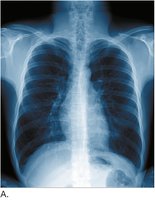

Chest x-rays are commonly used to visualize lung structure and diagnose conditions such as pneumonia, atelectasis, and tumors.